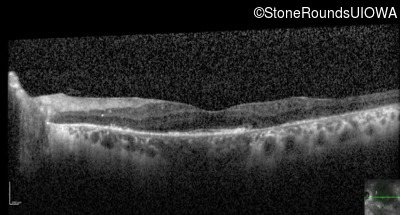

Optical Coherence Tomography - Right - 20/50 +2

Exemplar / OCT Stack